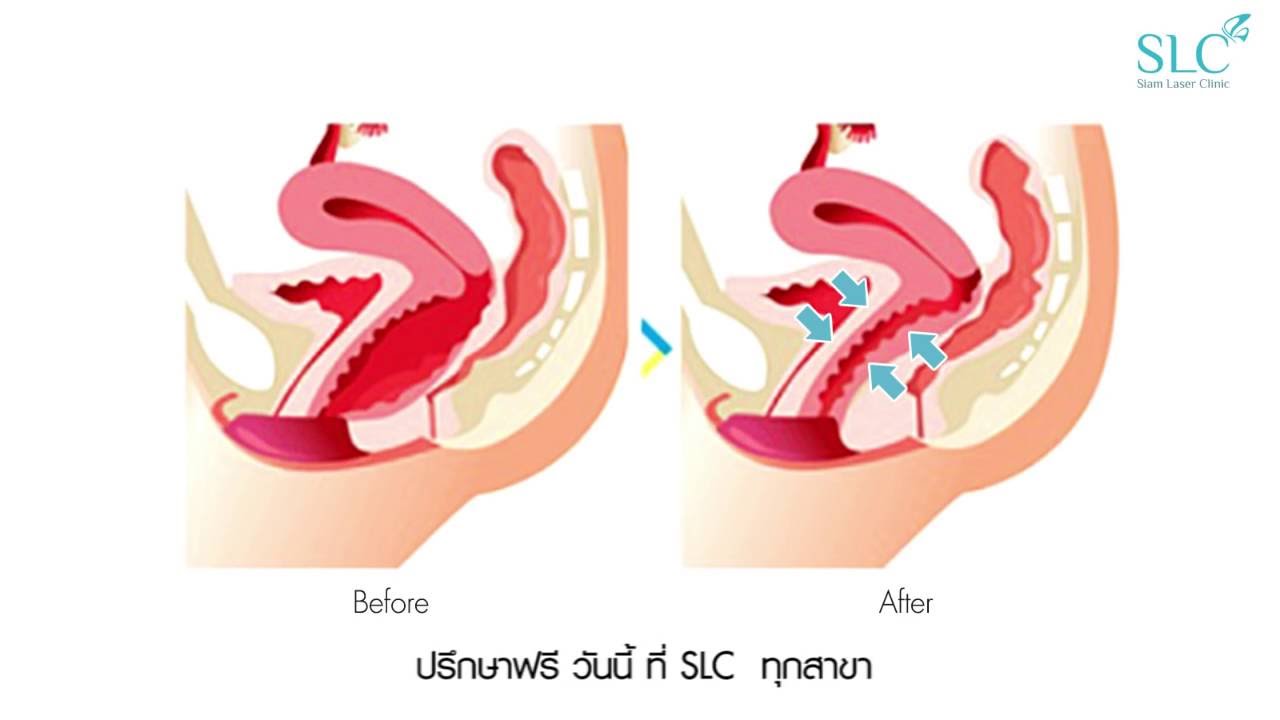

Омоложение влагалища

«Омоложение влагалища» включает в себя компоненты перинеопластики и вагинопластики и проводится для лечения «широкого» влагалища. Эти процедуры являются не чем иным, как модификациями существующих хорошо зарекомендовавших себя методов реконструктивной хирургии влагалища и тазового дна при кольпоперинеорафии, чтобы изменить калибр влагалища за счет уменьшения диаметра влагалищного канала наряду с реконструкцией тела промежности [23].

Вагинопластика предназначена для хирургического сужения влагалищного канала и включает удаление избыточной слизистой оболочки влагалища из сводов влагалища.Он может включать переднюю кольпорафию, заднюю кольпорафию, иссечение латеральной слизистой оболочки влагалища или различные комбинации этих хирургических методов (рис.). Некоторые хирурги также проводят пластику леватора по средней линии, чего, по нашему мнению, лучше всего избегать, так как это может вызвать выраженную диспареунию.

Фотографии до и после лабиопластики и омоложения влагалища

Омоложение влагалища

«Омоложение влагалища» включает в себя компоненты перинеопластики и вагинопластики и проводится для лечения «широкого» влагалища. Эти процедуры являются не чем иным, как модификациями существующих хорошо зарекомендовавших себя методов реконструктивной хирургии влагалища и тазового дна при кольпоперинеорафии, чтобы изменить калибр влагалища за счет уменьшения диаметра влагалищного канала наряду с реконструкцией тела промежности [23].

Вагинопластика предназначена для хирургического сужения влагалищного канала и включает удаление избыточной слизистой оболочки влагалища из сводов влагалища.Он может включать переднюю кольпорафию, заднюю кольпорафию, иссечение латеральной слизистой оболочки влагалища или различные комбинации этих хирургических методов (рис.). Некоторые хирурги также проводят пластику леватора по средней линии, чего, по нашему мнению, лучше всего избегать, так как это может вызвать выраженную диспареунию.

Фотографии до и после лабиопластики и омоложения влагалища